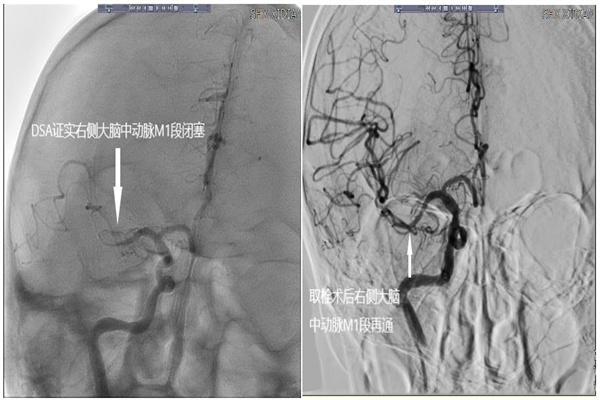

神經(jīng)內(nèi)科介入團(tuán)隊(duì)醫(yī)護(hù)人員迅速到位,穿刺過程順利。但由于張爺爺合并高血壓、糖尿病及長(zhǎng)期大量吸煙,動(dòng)脈硬化迂曲明顯而且是超級(jí)Ⅲ型弓,團(tuán)隊(duì)人員克服重重困難,順利將導(dǎo)絲導(dǎo)管到位,通過全腦血管造影術(shù)檢查,明確張爺爺右側(cè)大腦中動(dòng)脈閉塞。

術(shù)中,神經(jīng)內(nèi)科介入團(tuán)隊(duì)?wèi){著精湛的技術(shù)迅速將抽吸導(dǎo)管送至血管閉塞處,順利完成了取栓手術(shù),很快張爺爺血流恢復(fù),手術(shù)順利結(jié)束。術(shù)后,張爺爺肌力較前改善明顯。